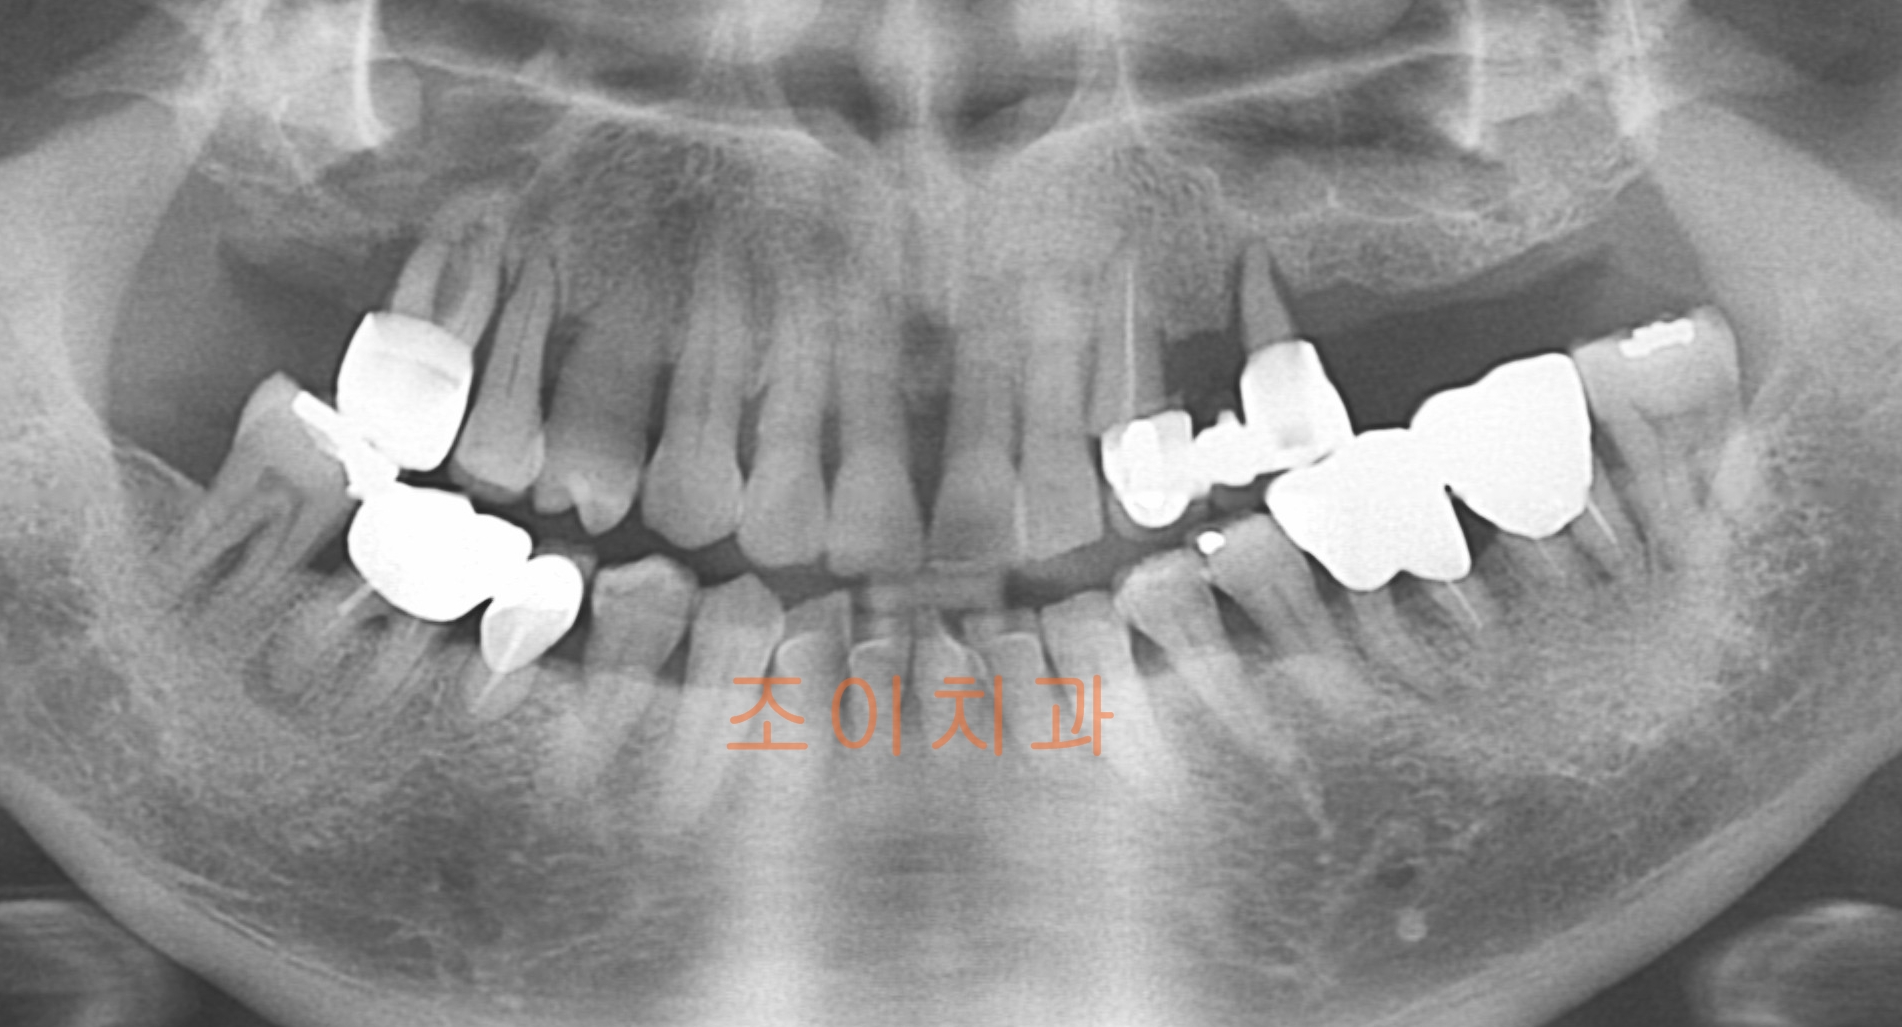

[임플란트] 제목 : 상악 임플란트

치주질환으로 인한 상악 임플란트 및 전반적 보철치료.